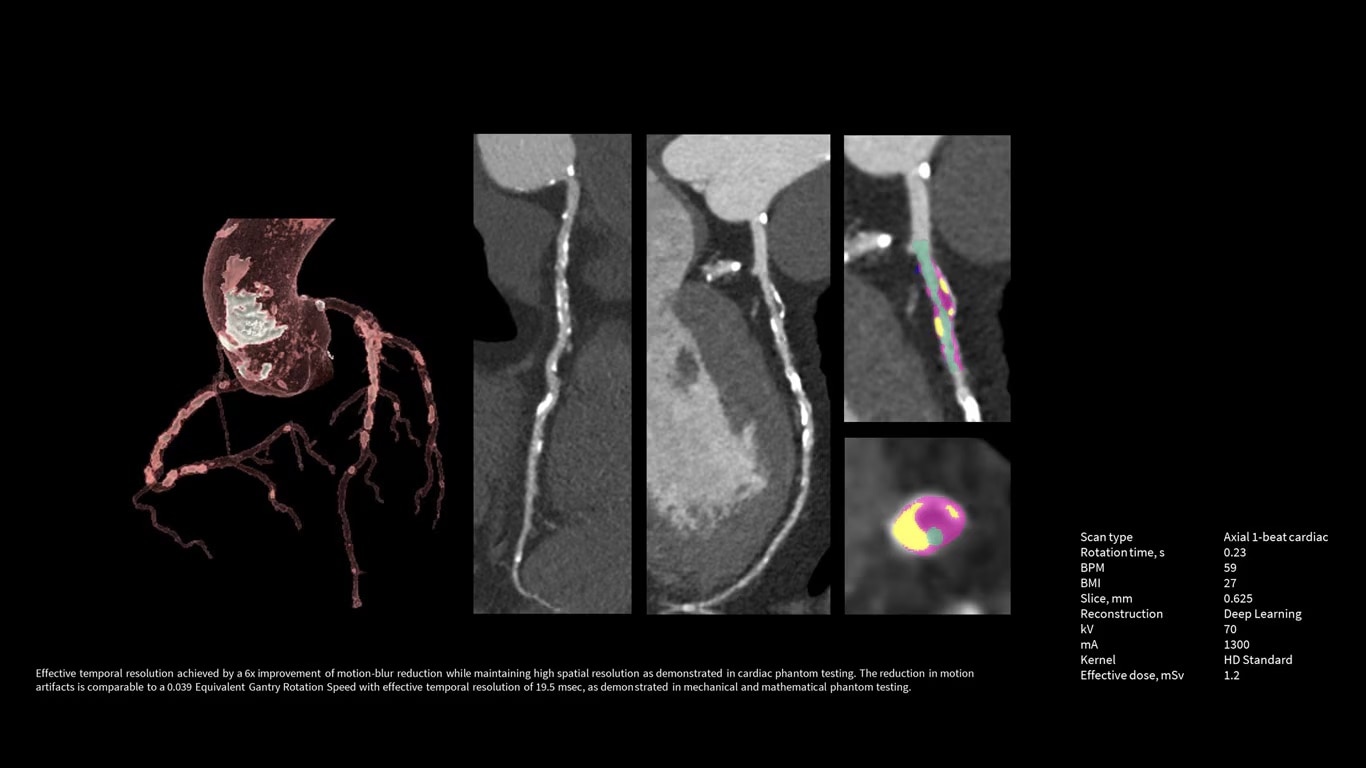

Upgrade to the industry's fastest rotation time

The Revolution Apex platform allows you to upgrade your gantry rotation speed. You can start with 0.28 sec gantry rotation time, and at any point in time when you need to advance your cardiac capability, you can upgrade to 0.23 seconds per rotation with the industry’s fastest rotation time.

The Revolution Apex platform provides high power output. The ability to upgrade means that siting challenges no longer prevent you from high power output to your department. If your siting power is limited to 150 KVA in the initial installation, you can start with the Power Pro option at maximum 1200 mA, and later on, you can scale up to 1300 mA Power Xtream when you upgrade the powerline.